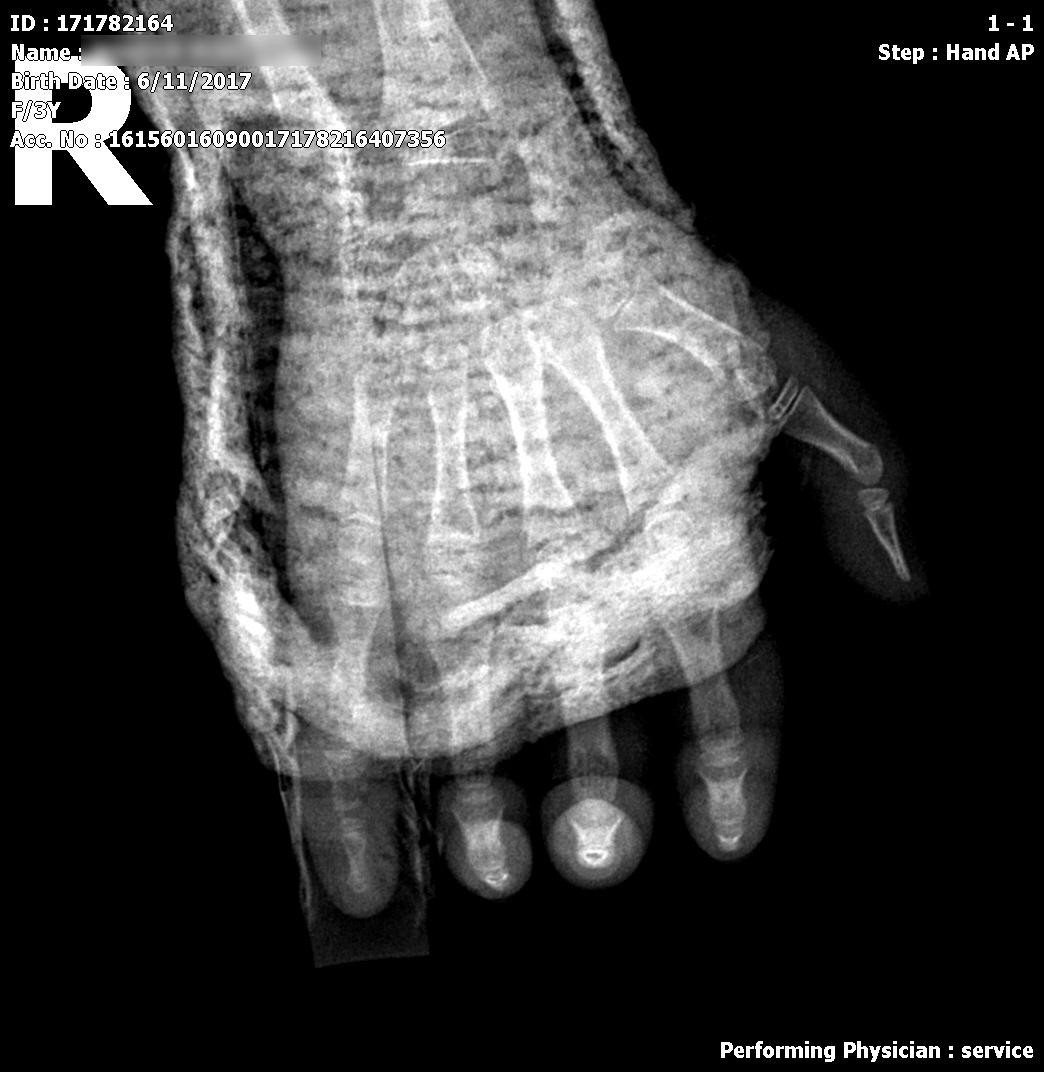

Kết quả chụp X-quang cho thấy bé bị gãy xương bàn tay phải số 3, 4, 5, không lệch. Tuy nhiên, các bác sĩ phát hiện vùng tụ máu lớn dưới da mu bàn tay phải hình thành ổ viêm hoại tử do lóc da kích thước 30x9,8x30mm có dấu hiệu sưng tấy lan rộng, thâm nhiễm mỡ xung quanh. Bàn tay phù nề nghiêm trọng.

| Ảnh chụp X-quang bàn tay phải bệnh nhi N.M.V ngày 13/3/2021 |